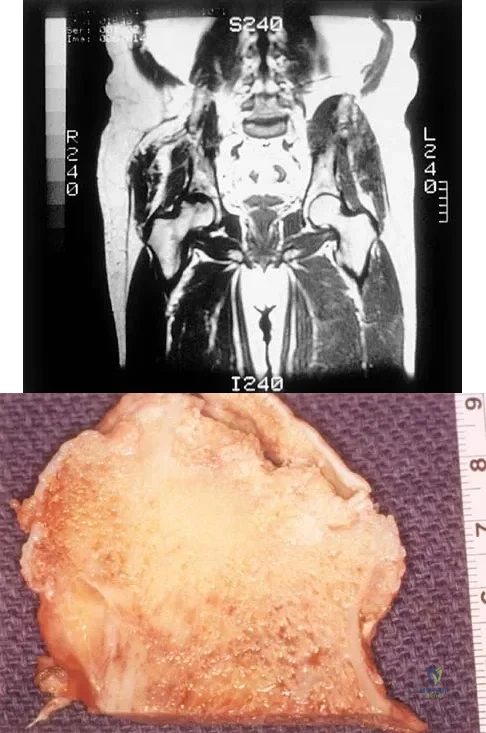

A 35-year-old patient has right hip pain. Figures 34a and 34b show the coronal MRI scan and the biopsy specimen. What is the most likely diagnosis?

Explanation